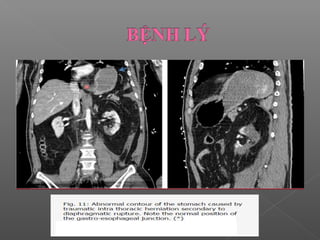

 Bất thường đường viền (Contour abnormalities):

Hay gặp

Nguyên nhân:

Hay gặp nhất là thoát vị dạ dày

Ít gặp: túi thừa dạ dày, lồng ruột.

 Bất thườngđường viền (Contour abnormalities): Hay gặp Nguyên nhân: Hay gặp nhất là thoát vị dạ dày Ít gặp: túi thừa dạ dày, lồng ruột.